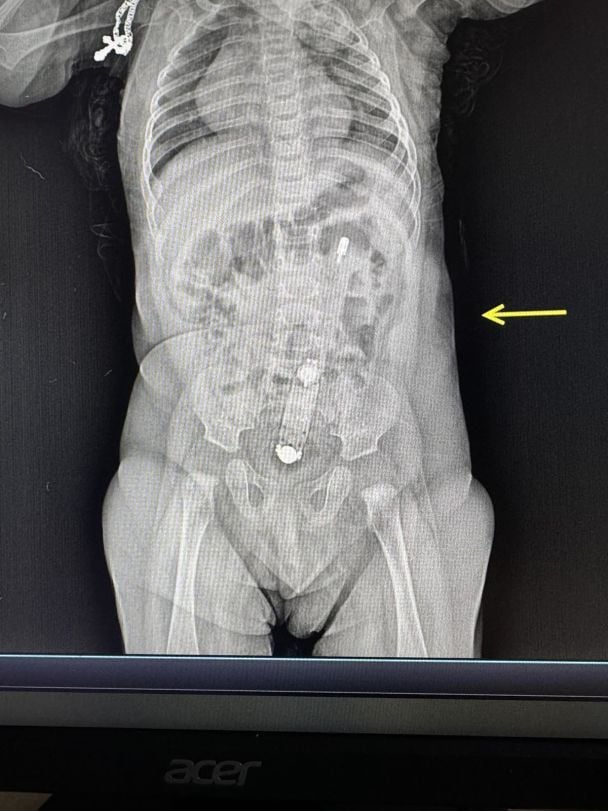

Достать термометр было очень непросто/Фото: Волынская областная детская клиническая больница

На Волыни мать пыталась сделать 6-месячному ребенку клизму с помощью электронного термометра, смазанного растительным маслом. Термометр полностью оказался в толстом кишечнике ребенка!

На рентгене был отчетливо виден термометр, также он пальпировался через живот.

"Достать прибор было очень непросто, – рассказывает хирург и эндоскопист Волынской областной детской клинической больницы Юлия Артишук. – Сделали это эндоскопически. Действовать нужно было очень осторожно, чтобы не травмировать младенцу анус и внутренние органы. Самостоятельно градусник выйти не мог, но мог перфорировать кишечник или в дальнейшем спровоцировать кишечную непроходимость".

На рентгене был четко виден термометр, также он пальпировался из-за живота/Фото: Волынская областная детская клиническая больница